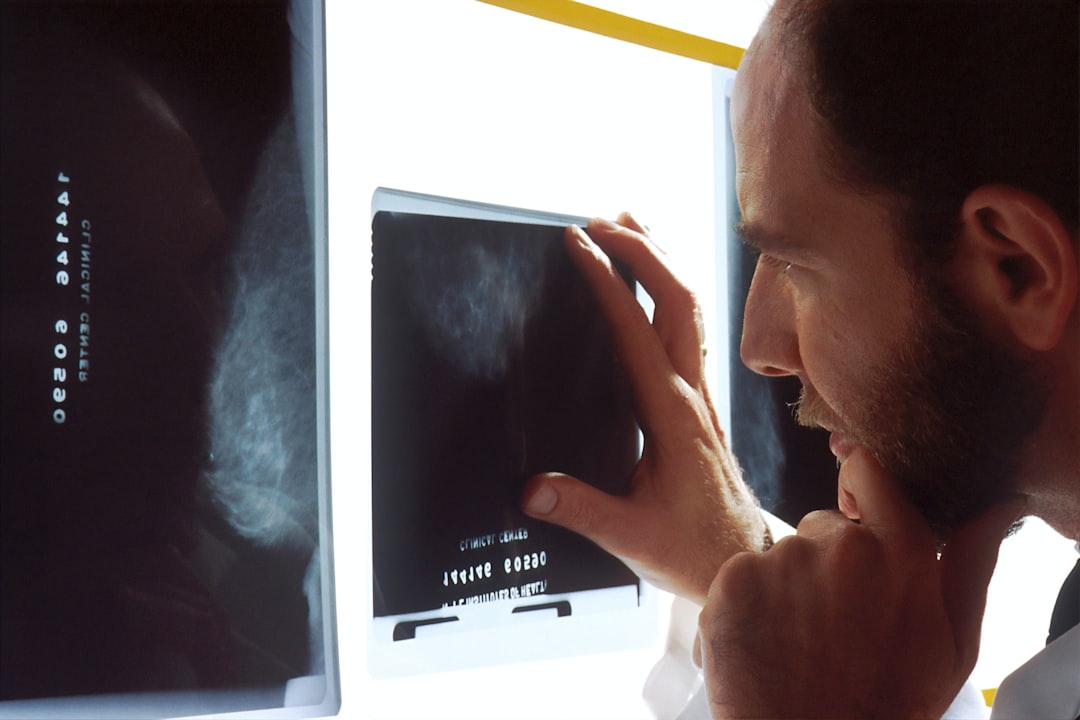

« Il était une fois, au pays des technologies désuètes, une épopée médicale emprisonnant nos précieuses imageries sur des CD-ROMs. » Pour beaucoup, obtenir une copie d’un scan ou d’une radiographie équivaut à un voyage dans le temps, direction les années 90, sans la bande-son cool. Mais une startup a décidé de pousser la porte du futur.

Le déclic ? Harsh Nayyar, co-fondateur, se blesse au tennis et reçoit les résultats de son scanner sur un CD. Entre nous, qui a encore un lecteur CD ? Inspiré par cette mésaventure technologique, lui et son frère, Rishi Nayyar, ont décidé de dépoussiérer le partage d’images médicales entre hôpitaux.

«Voilà 20 ans qu’on balade les patients entre A et B via un réseau fermé, avec un accès dérisoire à leurs propres données.» explique Rishi. PocketHealth, c’est l’engagement d’offrir plus d’accès, de contrôle et de compréhension de leurs dossiers médicaux aux patients.

Rishi souligne avec emphase l’évolution de PocketHealth : d’un simple archivage numérique à une complicité entre patients et professionnels grâce à un ajout de couche compréhensible pour naviguer dans le labyrinthe de la portabilité des données.